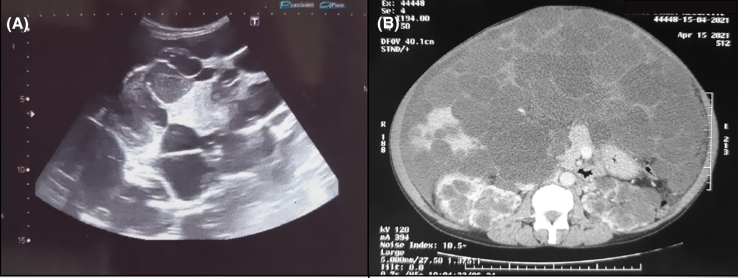

体格检查:明显腹胀、肝肿大,可触及多发囊肿。实验室检查示肝肾功能指标均正常。超声检查显示肝脏内存在多发囊性病变,内容物均匀一致,未见周围积液、囊肿破裂或出血迹象(图1A)。腹部CT

显示,肝实质几乎完全被大小不一的囊肿所取代,最大囊肿达11 × 5 cm(图1B)。未见腹水

征象。双肾均肿大,且广泛分布大小不一的多个囊肿。

图1 腹部超声检查示肝内多发囊肿(A);腹部CT示肝实质几乎完全被大小不等的囊肿取代(B)